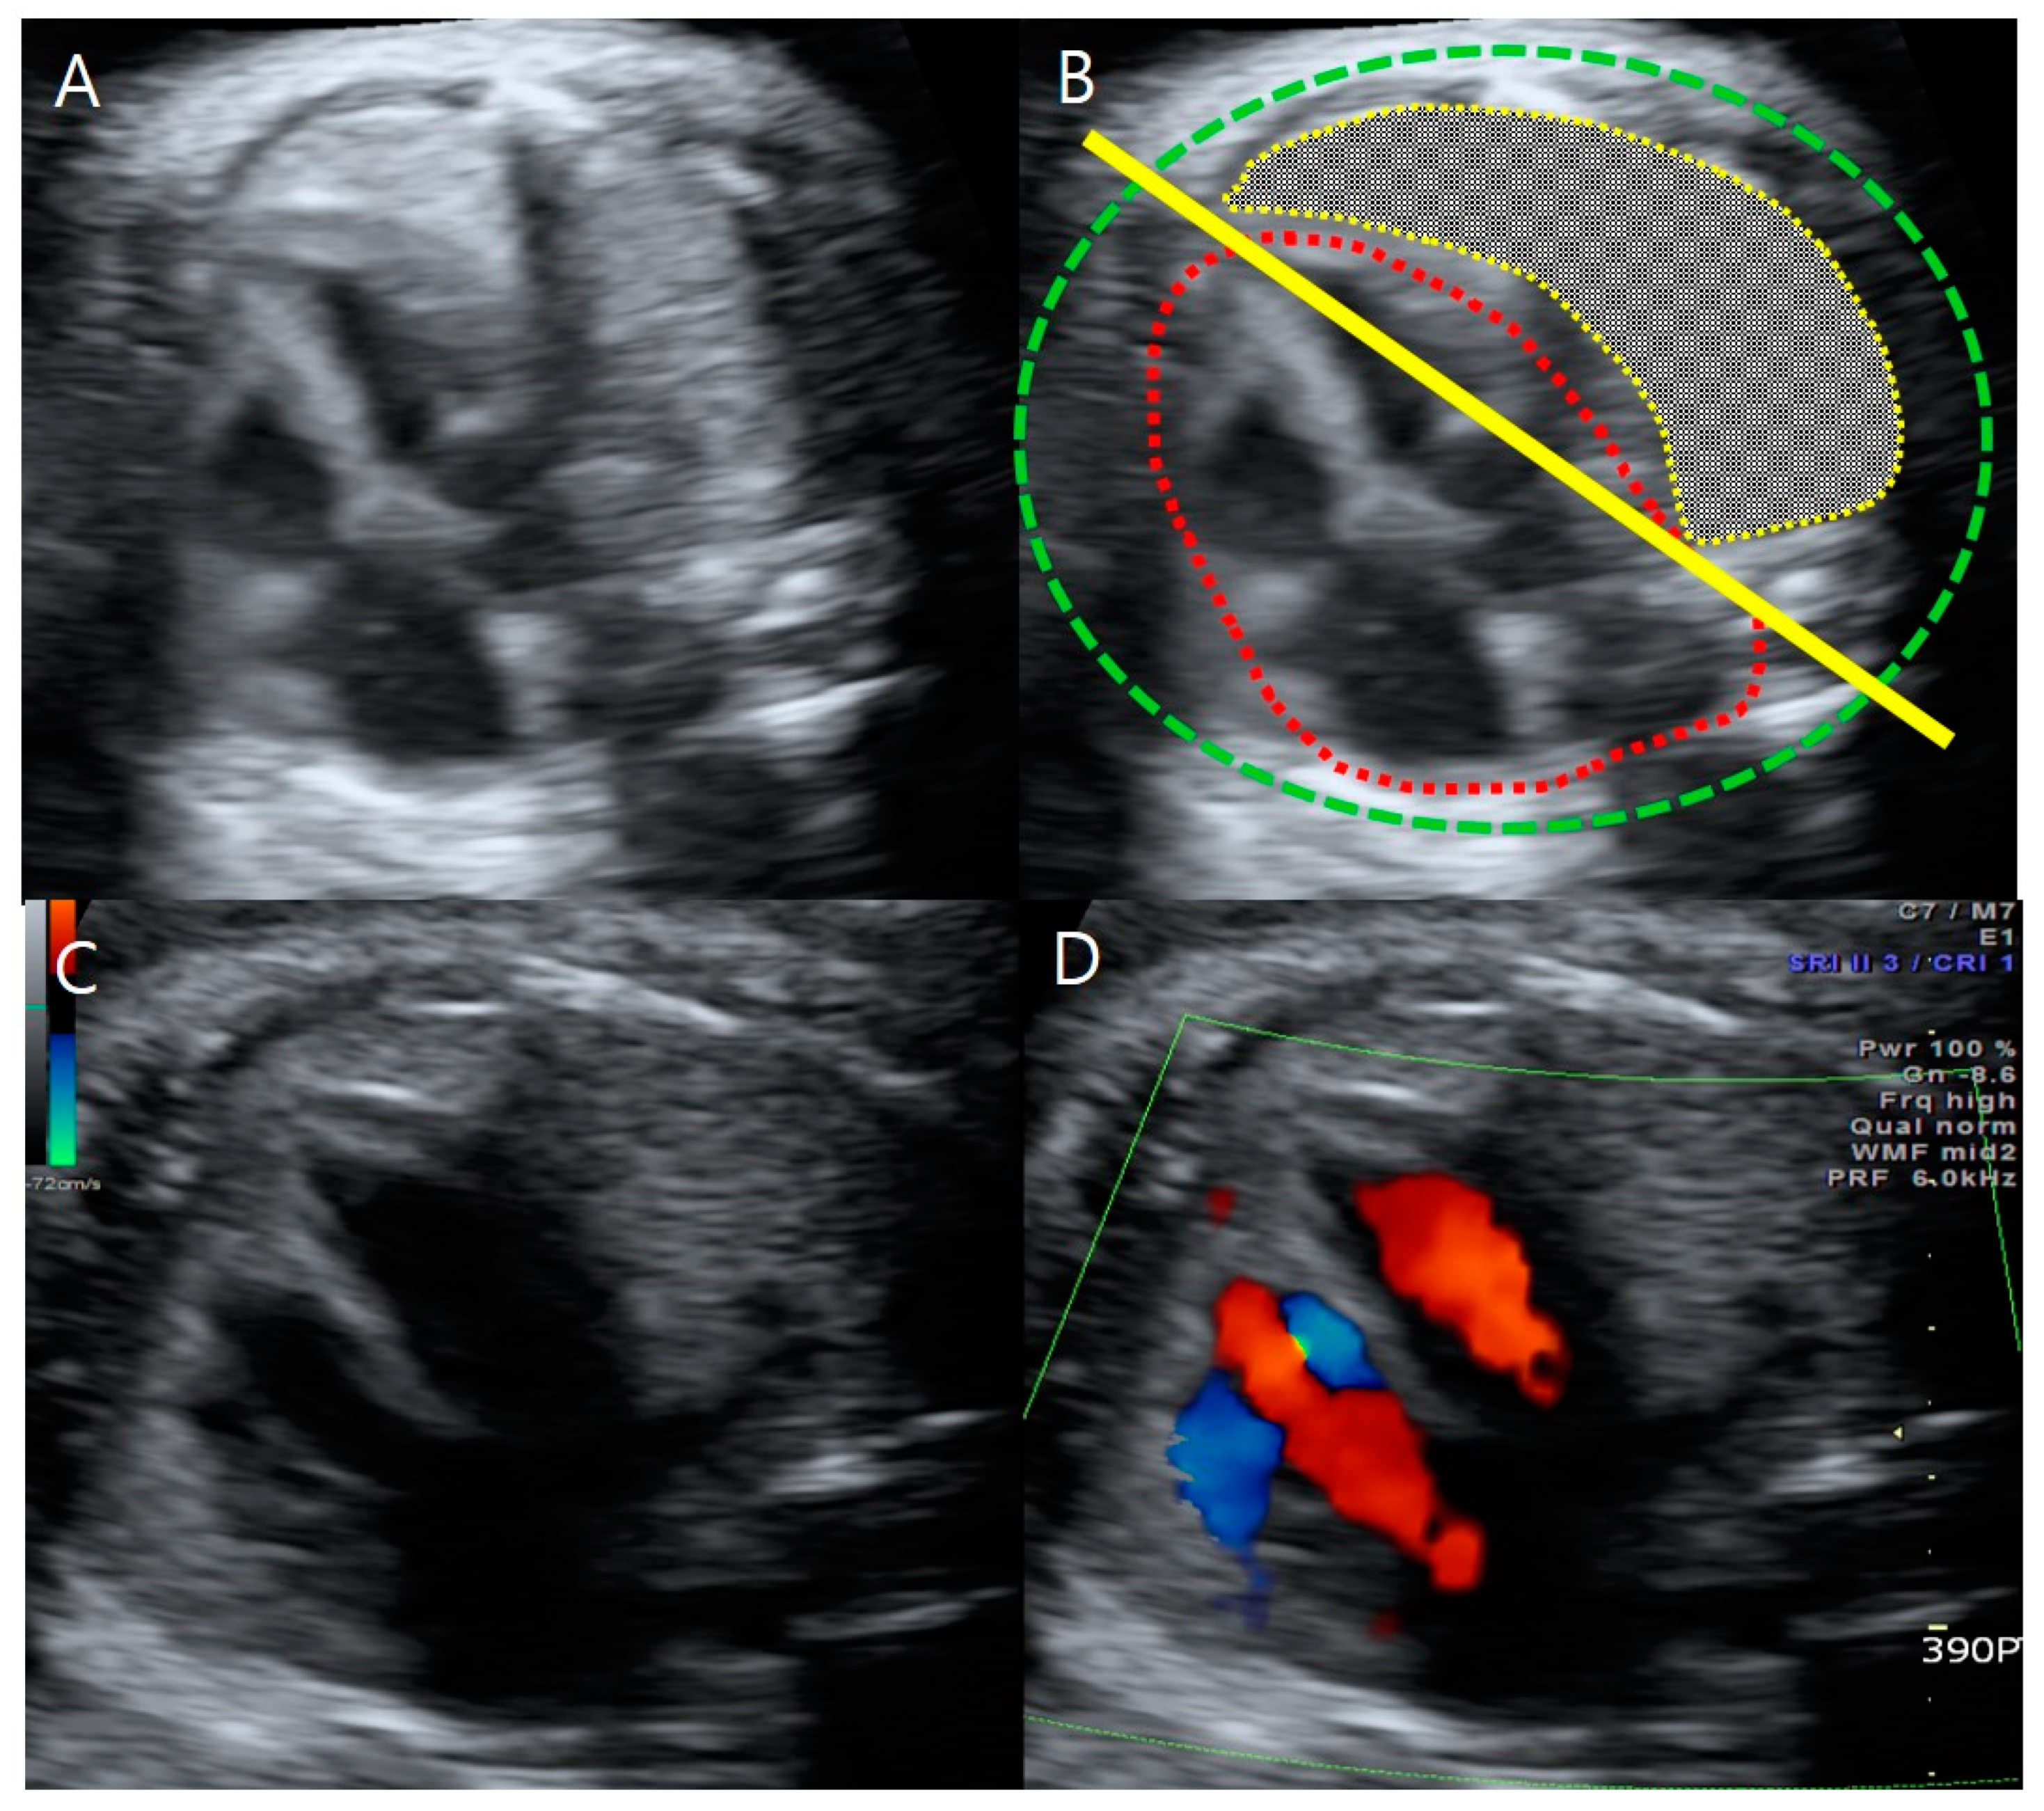

A detailed sonographic examination of fetus A detected a bilateral absence of the radii and thumbs (Figure 2). Both hands deviated in the direction of the absent bone, leading to an abnormally curved posture and radial clubhands. For the right forearm, we could not find the humerus because there was only one long bone proximally adjacent to the shoulder and distal to the curved hand.

Figure 2. Upper-limb anomalies of fetus A on ultrasonography at 31 + 3 weeks gestation. (A) The length of fetus A’s ulna was 2.63 cm (<5th percentile). (B) Fetus A’s humeral length was 4.63 cm (<5th percentile). (C) Fetus A’s forearm with the absence of radii, thumbs, and radial clubhands, or abnormally curved hands toward the absent bone.